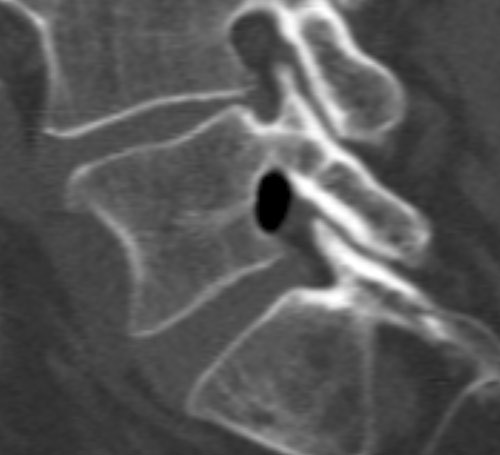

A man in his 60s was admitted to hospital with a two-day history of left-sided ischialgia and paresis development in L5 nerve innervated muscle. MRI showed a formation in the left lateral recess at L4/L5 level with dorsal dislocation of the left L5 nerve root. The formation had an unusually low MR signal giving rise to suspected calcification or the presence of air. A supplementary CT scan showed a well-defined collection of air in the same area (see images).

Clinical deterioration led to surgical exploration of the L5 root. Ventrally to the L5 root an amount of air was observable encapsulated in epidural soft tissue; an incision was made and the air released. Following this, the L5 root was softer to palpation and had free movement. The patient experienced considerable improvement postoperatively.

The presence of air in the intervertebral discs, known as the vacuum phenomenon, is a relatively common radiological finding in cases of degenerative changes in the lumbar spine. Cases are reported in the literature of gas in the spinal canal, in intervertebral foramina, in prolapsed tissue, epidurally and subarachnoidally, associated with the vacuum phenomenon (1). It may also occur secondary to degeneration in facet joints and ligaments.

In our patient, there was only low grade disc herniation without rupture in the anulus fibrosus and slight facet joint arthrosis at the levels concerned. The air may represent gas formation from a sequestrum from an earlier prolapse, alternatively a gas-containing pseudocyst associated with the vacuum phenomenon in adjacent intervertebral disc spaces. It is difficult on this basis to explain the acute onset case history, but incision and release of the air build-up in the patient was nevertheless therapeutic.